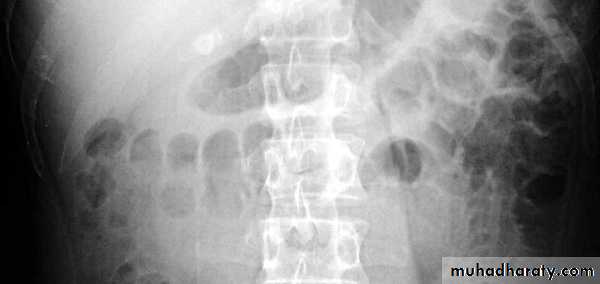

Radiological features of toxic megacolon :

• The colon (typically transverse colon) becomes dilated to at least 6 cm (usually greater). There is additional loss of haustral markings

• It is serious acute abdominal condition

• More in UC > CD

• Practical points

• barium studies and colonoscopy should be avoided, due to the risk of perforation